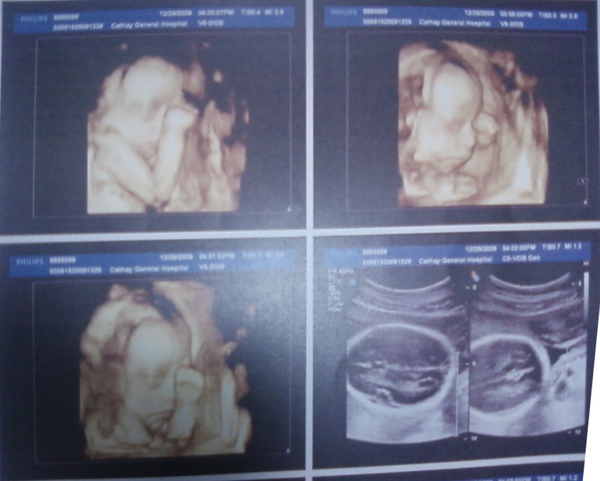

台北國泰的高層次超音波檢查固定是在星期二、四的下午,要先預約時間,檢查的醫生都是周靜玉醫生,自費費用2500元,檢查時間大約15分鐘,扣除等待前一位出來的時間,在加上聽報告的時間,大概只花了20~25分鐘。不知道為什麼沒有很超值的感覺,大概是因為檢查的時間跟19W2D健保給付的超音波檢查時間差不了多少吧!

跟19W2D健保給付的超音波檢查不一樣的地方是,他會先給你照幾張3D寶寶的臉給你紀念,也可以順便看看是否有兔唇之類的狀況。